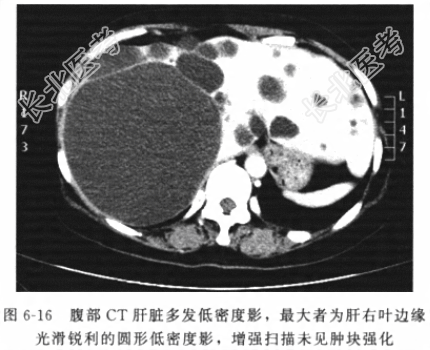

- [材料题] 患者男性,48岁,因“上腹部饱胀不适伴纳差1年”入院。患者1年前出现上腹部饱胀不适锌纳差,进食后加重,无反酸、嗳气、畏寒、发热及恶心、呕吐等其他伴随不适。近一个月来,症状加重,进食多后更为明显。发病来,一般情况可,无明显体重减轻。否认有“胃炎”、“胆囊炎”、“肝病史”。体格检查体温(T)36.6℃,呼吸(R)20次/分,脉搏(P)81次/分,血压(BP)121/70mmHg。神志清楚,皮肤干燥,巩膜无黄染。腹平软,未见胃肠型或蠕动波,Murphy征(-),全腹未能扪及包块,肝肋下未及,移动浊音(-),肠鸣音无亢进或减弱。蛊肠指检未及异常占位,退出时指套无染血。辅助检查三大常规、肝肾功能、病毒、电解质、凝血功能、血气分析结果均未见明显异常。腹部B超提示肝脏多发无回声液性暗区,最大位于肝右叶大小约10cm×10cm×8cm边界清晰的无回声液性暗区。腹部CT平扫(图6-16)示肝脏多发低密度影,最大者肝右叶边缘光滑锐利的圆形低密度影,增强扫描未见肿块强化。